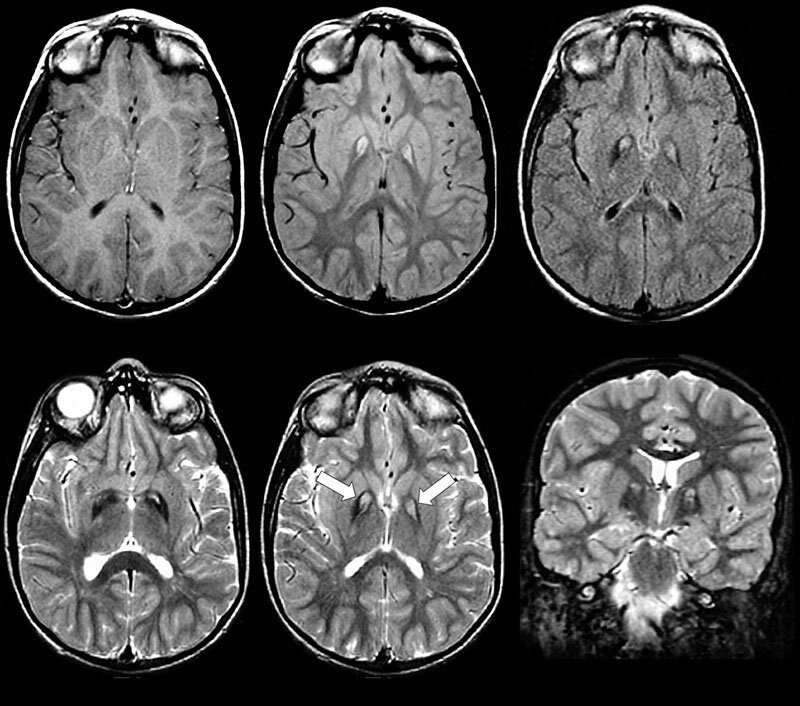

МРТ головного мозга. Источник: vsemrt.ru